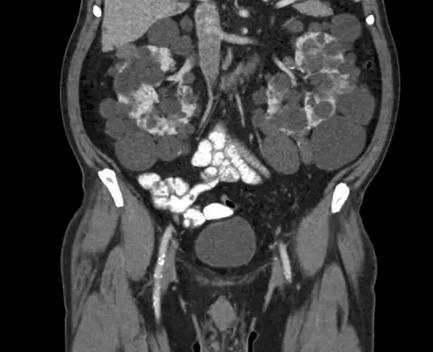

Компьютерная томография демонстрирует поликистоз почек и печени

Органы брюшной полости, ретроперитонеального пространства. КТ живота является точным методом для диагностики абдоминальных патологий:

опухолей (КТ показывает стадию и распространенность рака, ответ на лечение).

КТ брюшной полости является современным и точным рентгенологическим способом диагностики органов, расположенных в брюшной области. Во время обследования происходит томографическое, то есть, послойное сканирование исследуемой зоны. Современные мультспиральные томографы способны за один оборот сканера делать от 32 до 640 срезов, а мощный компьютер может создать трехмерные реконструкции всех анатомических структур области живота. Данные КТ снимков позволяют выявить воспалительные процессы и опухолевые изменения в костных и мягкотканных структурах.

Процедура компьютерной томографии органов брюшной полости проходит по двум базовым протоколам — нативная и контрастная. МСКТ с контрастным усилением предполагает использование контрастных препаратов на базе йода, которые улучшает тканевую контрастность на томограммах и позволяет определить новообразования на этапе развития. Кроме того, существует агиографическая форма обследования (КТ брюшной аорты и сосудов) области живота, когда врачи прицельно оценивают сосудистую систему брюшной полости.

Что показывает МСКТ органов брюшной полости

КТ обследование брюшной полости и забрюшинного пространства помогает выявить ряд заболеваний:

КТ брюшной полости с контрастом

КТ брюшной полости с контрастом способствует наиболее четкому отображению тканей и часто используется при онкопоиске. Контрастирование позволяет установить опухолевые очаги и степень их распространения на соседние участки. Контраст распространяется в крови и как бы “подкрашивает” ткани. Обязательного контрастного усиление потребует КТ ангиография сосудов брюшной полости. Без контрастирования сосудистая сеть на компьютерной томографии не видна.